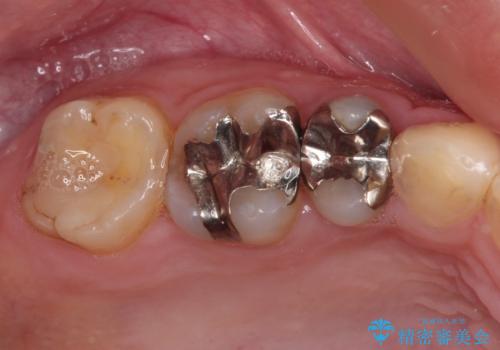

- 他院で抜歯矯正を終えた後、銀色の目立つ奥歯を白くしたいとのことで来院された患者様です。

既にセラミッククラウンが装着されている歯もありますが、不自然な色合いや黒い縁も気になるので、一斉に補綴治療をして統一感を持たせることとしました。